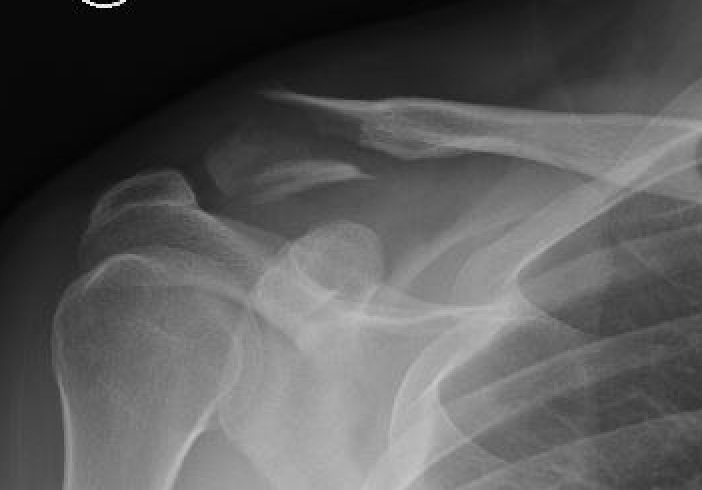

Neer Classification

Fracture lateral to the CC ligaments Non displaced

Fracture medial to the CC ligaments CCL ligaments attached to lateral fragment Medial fragment displaced superiorly |

Between conoid and trapezoid Conoid disrupted Trapezoid remains attached to the lateral fragment |

Lateral to CC ligaments Intra-articular extension Stable |

Periosteal sleeve disruption Pediatric Medial fragment displaced |

Comminuted Type II Medial fragment displaced |

Type I

Type II

Type V